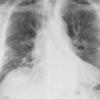

Gallery Pulmonary Fibrosis IPF

IPF